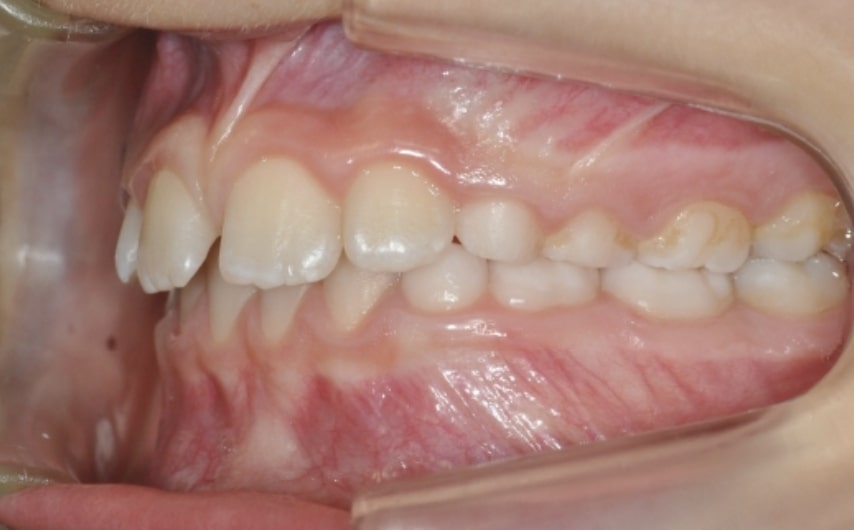

Section Class II division 1 malocclusion

Malocclusion A6 Correction of Mandibular Retrusion in Growth phase patient | Skeletal Class II | Class II Division 1 malocclusion | Deep bite | Mixed dentition

Clinical examination and diagnosis

- Molar and Canine class 2 on the right side – Molar and Canine clss 1 on the left side

- Increased Overjet

- DeepBite

- Reduced Transversal Diameters